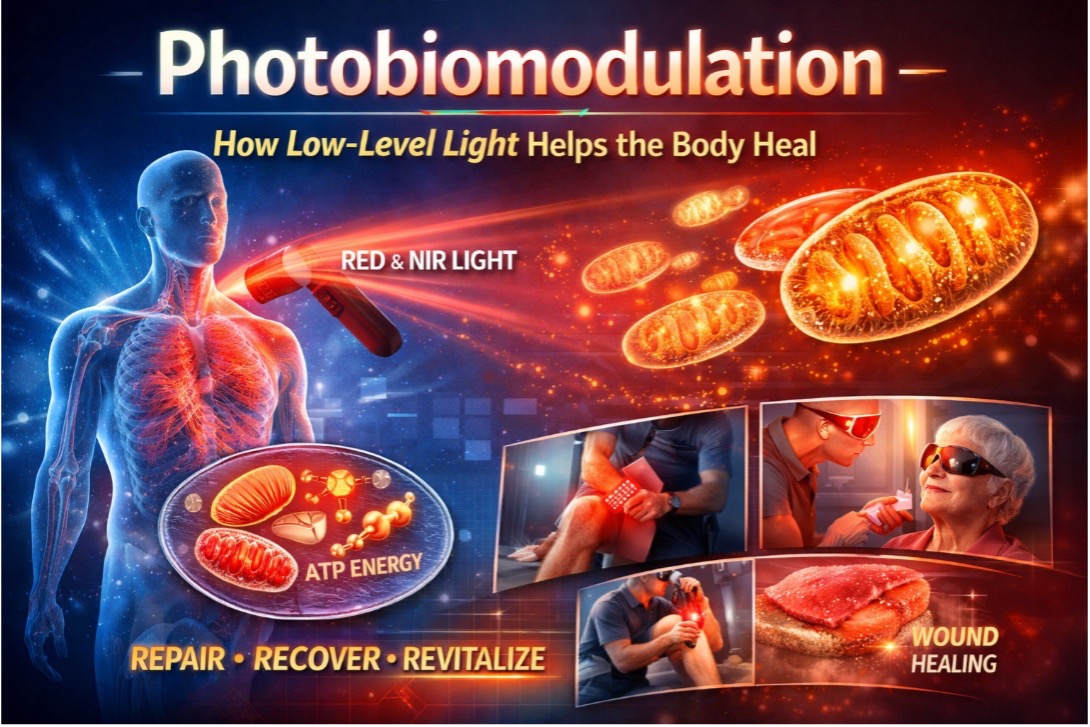

Per trarre pieno beneficio da questa unità di apprendimento sulla Fotobiomodulazione (PBM), gli studenti dovrebbero avere una conoscenza di base della biologia umana, inclusi cellule, mitocondri e metabolismo energetico. La familiarità con le proprietà della luce, come lunghezza d’onda e intensità, aiuterà a comprendere come la luce rossa e quella vicino all’infrarosso (NIR) interagiscono con i tessuti. Gli studenti dovrebbero inoltre essere a proprio agio con gli ambienti di apprendimento digitali e l’uso di strumenti interattivi, poiché l’unità include simulazioni in Realtà Aumentata (AR), quiz ed esercizi pratici. Si incoraggiano il pensiero critico e la curiosità per analizzare le osservazioni e riflettere sulle applicazioni reali della PBM in ambito sanitario, sportivo e nella vita quotidiana. Non è richiesta alcuna esperienza precedente con la fototerapia, ma un interesse nell’esplorare come la luce a bassa intensità possa stimolare i processi cellulari e supportare la guarigione dei tessuti arricchirà l’esperienza di apprendimento.